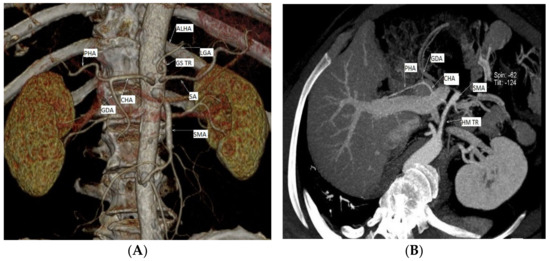

Studying the level of origin of RCHAs in the 76 cases, we revealed three distinct morphological types. In their order of frequency, the origin of the RCHA was present at the level of: (i) the abdominal aorta (AA)—69 cases (90.78%); (ii) the superior mesenteric artery (SMA)—6 cases (6.89%); and (iii) the left gastric artery (LGA)—1 case (1.31%) (Figure 1).

Figure 1.

Three distinct types of level of origin of the replaced common hepatic arteries. Replaced CHA origins at the level of: (A) the abdominal portion of the aorta; (B,C) the superior mesenteric artery; (D) the left gastric artery (personal casuistry). (A) Male patient, 75 years old, with a diagnosis of peripheral arterial disease (PAD); (B) male patient, 66 years old, with a diagnosis of critical limb ischemia; 3D reconstruction, for a better view of the described arteries we used gantry tilt/spin (degrees -124/42) (C) male patient, 70 years old, with a diagnosis of chronic kidney disease; (D) male patient, 73 years old, with a diagnosis of PAD. Abbreviations: ALHA—accessory left hepatic artery, CHA—common hepatic artery, CT—celiac trunk, GS TR—gastrosplenic trunk GDA—gastroduodenal artery, HM TR—hepatomesenteric trunk LGA—left gastric artery, LHA—left hepatic artery, PHA—proper hepatic artery, SMA—superior mesenteric artery, and SA—splenic artery.

In the first group, with RCHAs arising from the AA, we included two subgroups: (i) 20 cases with the absence of the CT as a morphological entity (independent origin of the CHA, the LGA and the SA in the AA) and (ii) 49 cases with the association of a gastro–splenic trunk with the independent origin of the CHA from the AA. We studied the vertebral level of the origin of these 69 cases with RCHAs arising from the AA, and observed that most of the arterial trunks of the CHA originated between the intervertebral disc T12/L1 and the middle 1/3 of the body of the first lumbar vertebra, also with an extension range between the middle 1/3 of the twelfth thoracic vertebra (T12) and the upper 1/3 of the second lumbar vertebra (L2) (69.56%; 48/69 cases). The endoluminal diameter of the RCHA at its origin averaged 0.42 cm, with a range between 0.23 and 0.6 cm.

Discussing the second group, with RCHAs arising from the SMA, we observed that the distance between the origin of RCHA and the origin of the source trunk showed an average of 3.44 cm, with a variation range from 2.34 to 4.51 cm; the endoluminal diameter of RCHA at its origin averaged 0.49 cm, with a range between 0.39 and 0.66 cm.

In the third group, with RCHAs arising from the LGA, the distance between the origin of the RCHA and the origin of the source trunk was 3.31 cm, while the endoluminal diameter of the RCHA at its origin was 0.25 cm.